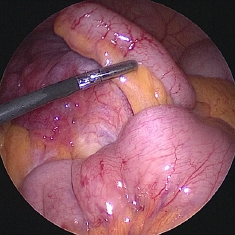

図2 虫垂を捉えたところ

図3 超音波切開装置で間膜処理

図4 虫垂を結紮して切離したところ